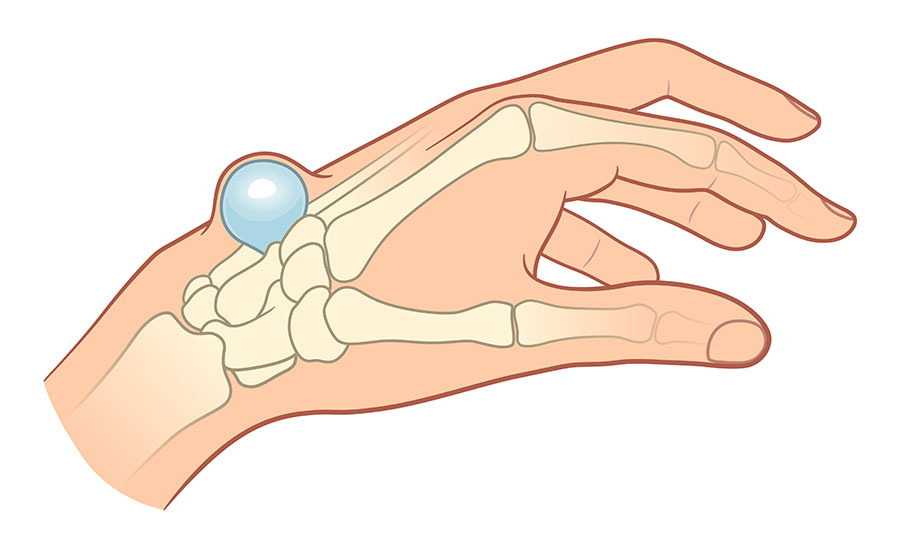

Ganglion eltávolítás

kisműtét

A ganglion eltávolítás (Ganglion exstirpatio) során a kézháton vagy a lábfejen kialakult folyadékkal telt ganglion cisztát műtéti beavatkozás keretében, az érintett testrész helyi érzéstelenítése mellett távolítjuk el.